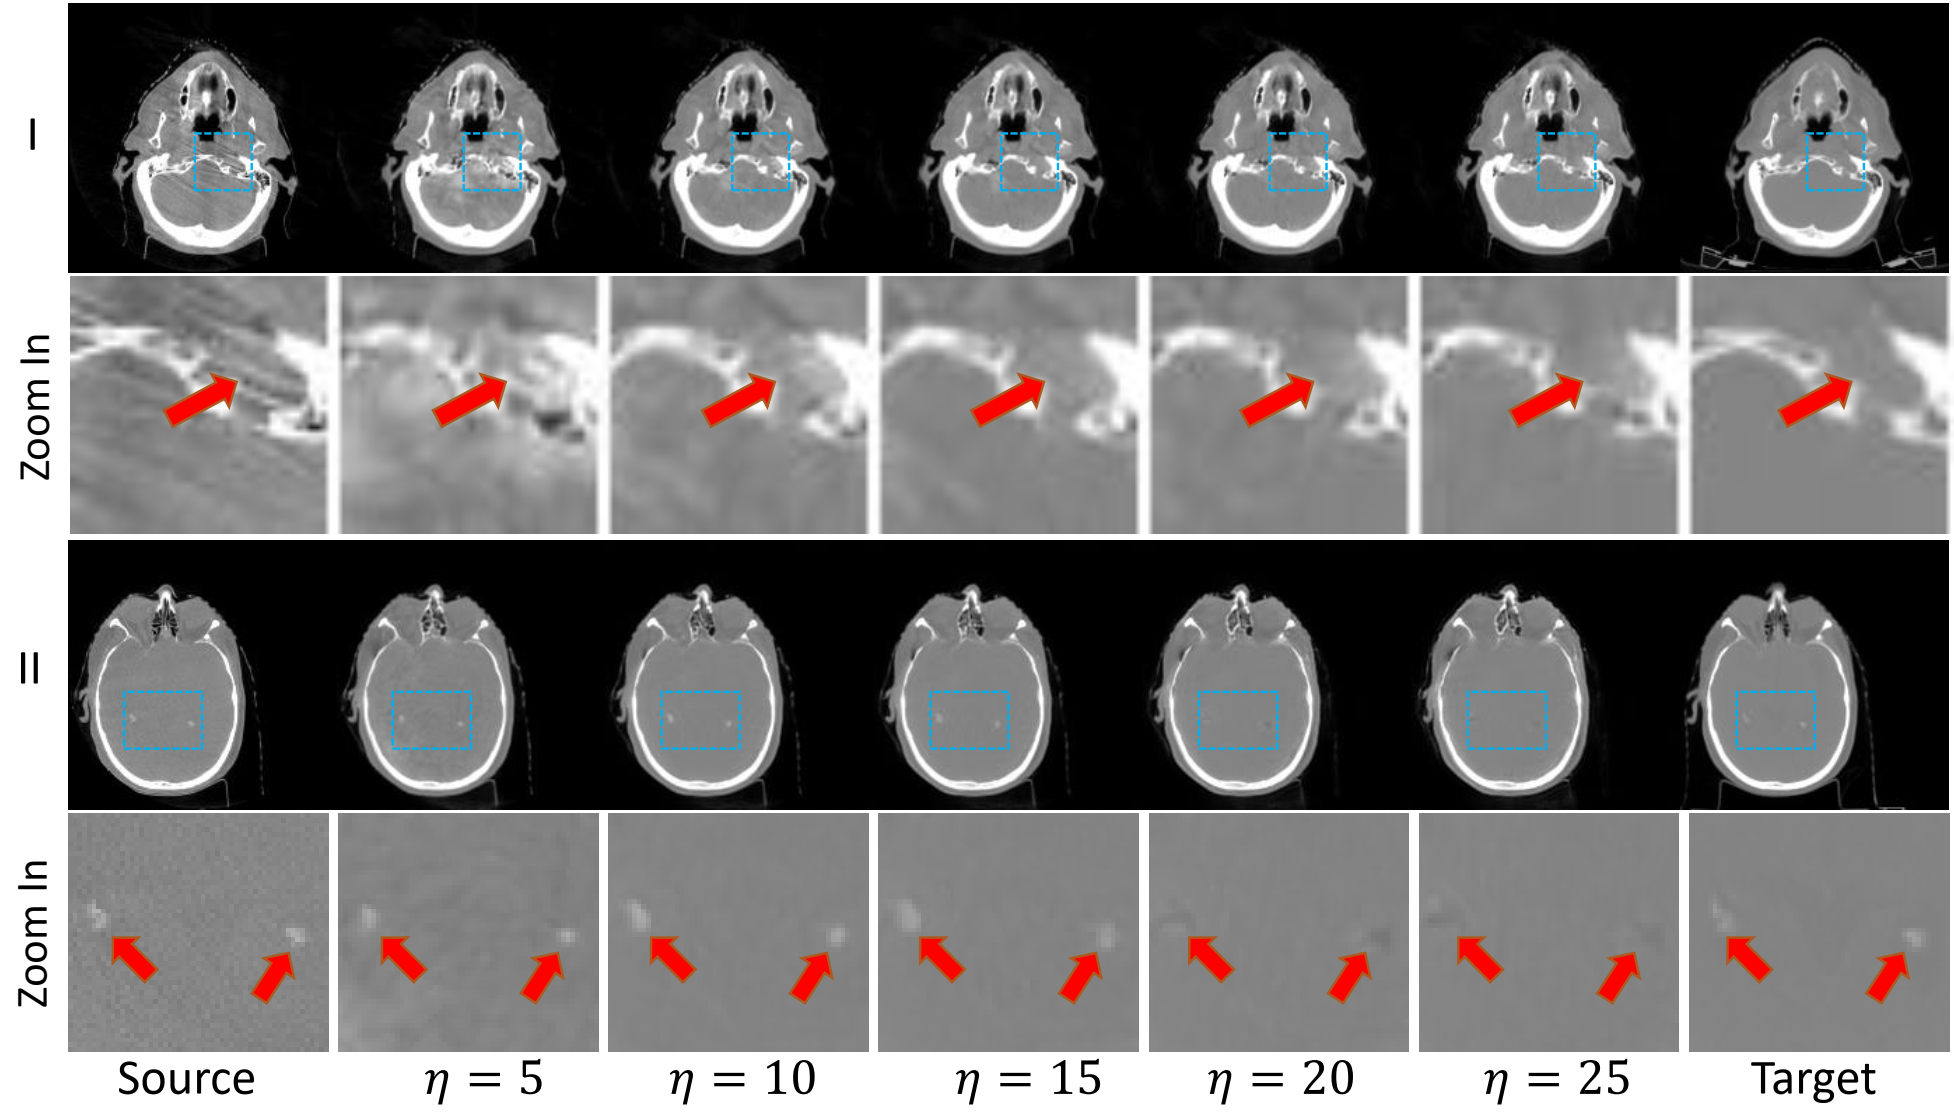

Refer to caption

Figure 9: Visual comparison between images generated using different values of high-frequency ratio parameter η𝜂\eta on the head and neck dataset. The display window is [-1000,1000] HU.

4.8.2 Impact of the high-frequency ratio parameter η𝜂\eta

For FGDM, the high-pass filter has an adjustable η𝜂\eta parameter that can be customized on-the-fly during the test time to fit different image translation tasks. Since the data in the source and target domains differ in frequency space for different image translation tasks, retaining appropriate high-frequency information can both filter out undesired information, like artifacts in CBCT, and preserve the anatomical structure. As shown in Table 6, the model achieves optimal performance when η𝜂\eta equals 10. As η𝜂\eta increases further, more information is filtered out by the high-pass filter, resulting in insufficient high-frequency guidance for structure retention, shown in Fig. 9(II). When η𝜂\eta is smaller than 10, the high-frequency information contains more artifacts, resulting in degraded model performance, shown in Fig. 9(I). During the test time, η𝜂\eta can be freely adjusted by the user to select an optimal value for each case.